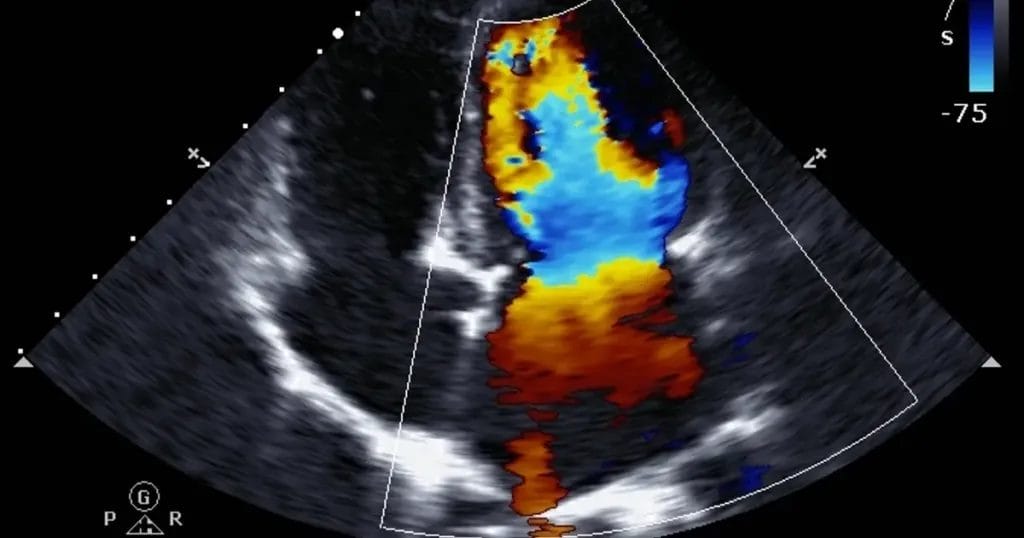

ولذلك ينصح الأستاذ الدكتور محمد الغنام بإجراء فحوصات إضافية لتأكيد تشخيص ضيق الشريان التاجي مثل: موجات صوتية على القلب، والتصوير المقطعي المحوسب، واختبار الجهد، وتصوير الأوعية الدموية.

و لهذا السبب، يوضح الأستاذ الدكتور محمد الغنام أن نتيجة رسم القلب الطبيعية لا تنفي وجود أمراض قلبية أخري خطيرة، خاصةً إذا كانت هناك أعراض، وفي تلك الحالة يجب إجراء فحوصات أخرى، مثل: اختبار الجهد، والايكو، تصوير الأوعية التاجية المقطعي المحوسب (CT)، التصوير بالرنين المغناطيسي للقلب (MRI)، و تصوير الأوعية التاجية.

- الإيكو.